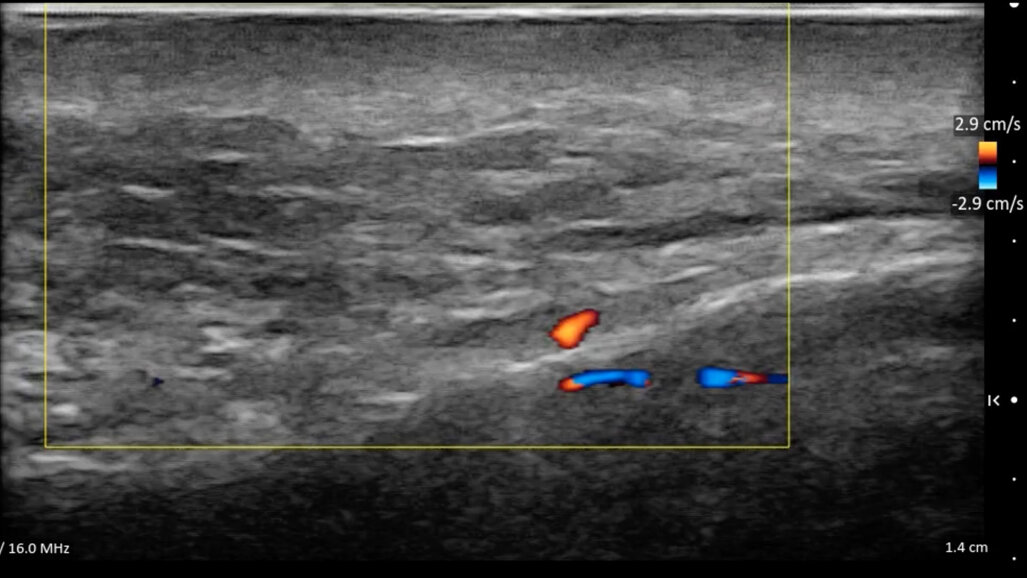

• Mappatura vascolare dinamica: l’integrazione di B Mode, Color Doppler e del Power Doppler rappresentano la frontiera della sicurezza. Vasi critici posti in posizioni anatomiche critiche come l’arteria angolare possono avere decorsi variabili. L’esame ecografico permette di mappare questi vasi prima di inserire l’ago, scegliendo il piano di correzione (superficiale o profondo) che garantisca l’assenza totale di rischio vascolare occlusivo intravascolare o compressivo extravascolare (Fig. 9).

Fig. 9 - L’arteria angolare in Color Doppler.